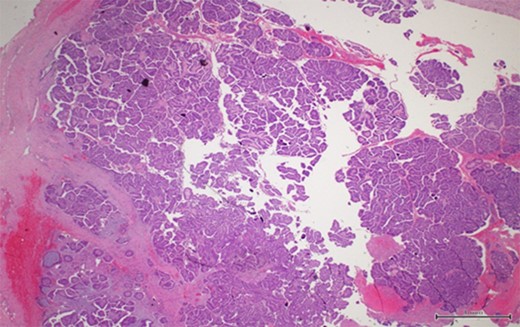

Ultrasound studies showed a well-defined solid-cystic nodule measuring approximately 2.1 cm × 2.1 cm × 1.4 cm with internal septation. There was a large, peripherally located solid component with internal vascularity seen (Fig. 2). The lesion was deemed indeterminate and an excision biopsy was performed. The histology report revealed a Grade 1 IPC with no lymphovascular invasion (Figs 3 and 4).

A thick fibrous wall surrounding a cystic space with a complex and arborizing papillary network within (magnification x2).